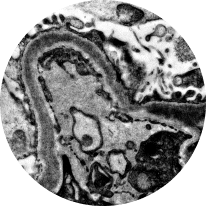

Electron microscopy

Distinguishes between C3G subtypes: dense deposit disease (DDD) and C3 glomerulonephritis (C3GN). Of the 2, DDD typically progresses more rapidly2,22

DDD

C3GN